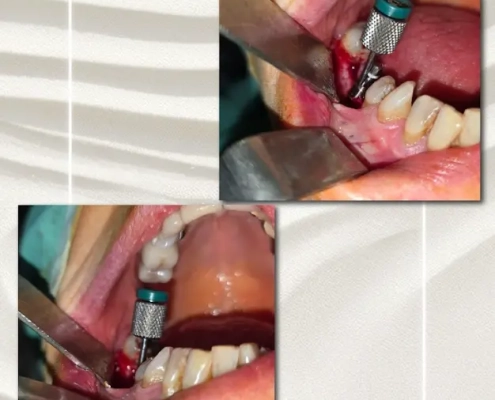

Cas clinique du Dr. Benat avec les Implants Co-Axis®

Le cas clinique met en évidence une insuffisance de volume osseux avec un axe implantaire défavorable en secteur postérieur, objectivée sur l’imagerie 3D et la radiographie panoramique, compromettant un positionnement implantaire axial conventionnel sans compromis prothétique.

Avec la collaboration du Dr. Gauthier Benat